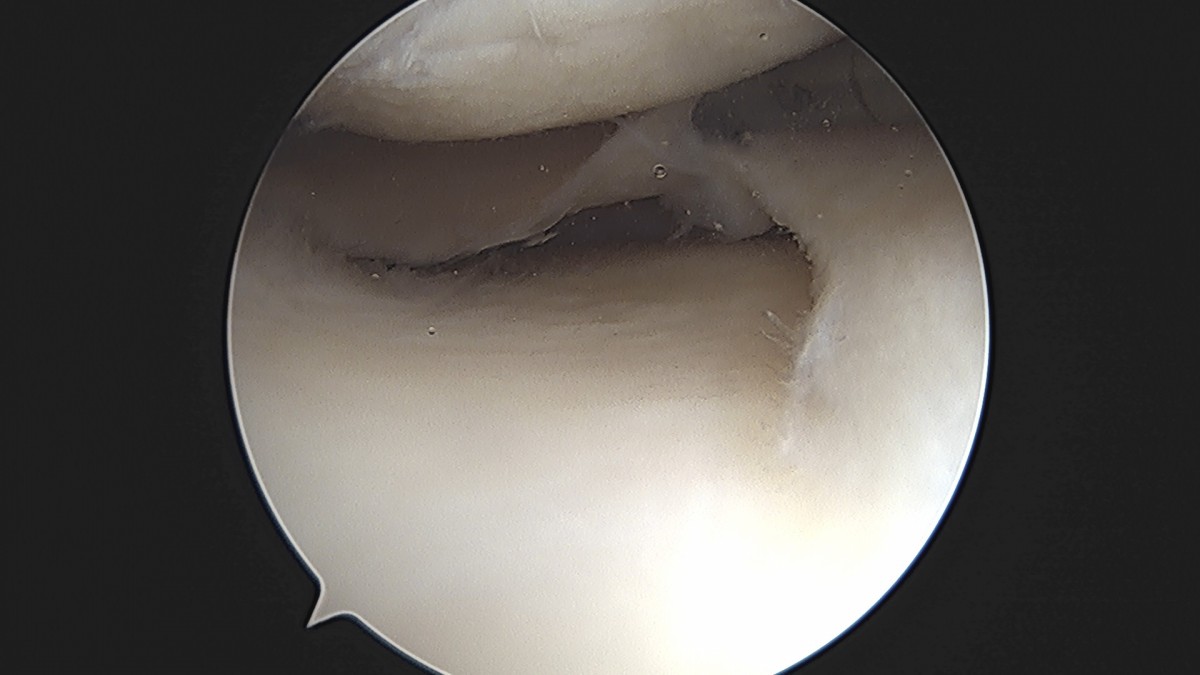

이재상원장님 무릎 반월상 연골판 절제술 박강O 환자

dae765e4d9ac96aee867c9d6292d8784_1758005269_3478.jpg